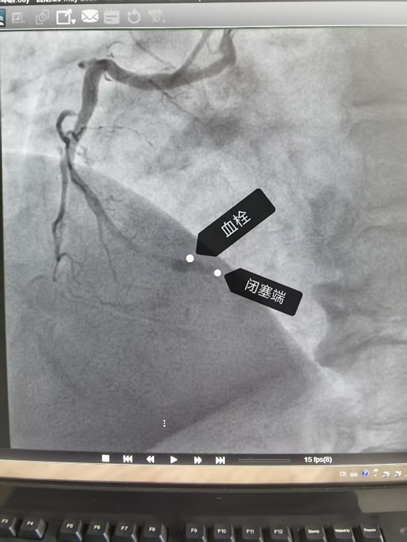

经过紧张抢救,手术团队成功为李先生实施了冠状动脉介入手术,疏通了完全堵死的右冠脉,并植入支架。目前,李先生恢复良好,生命体征平稳。

△堵住患者右冠脉的血栓